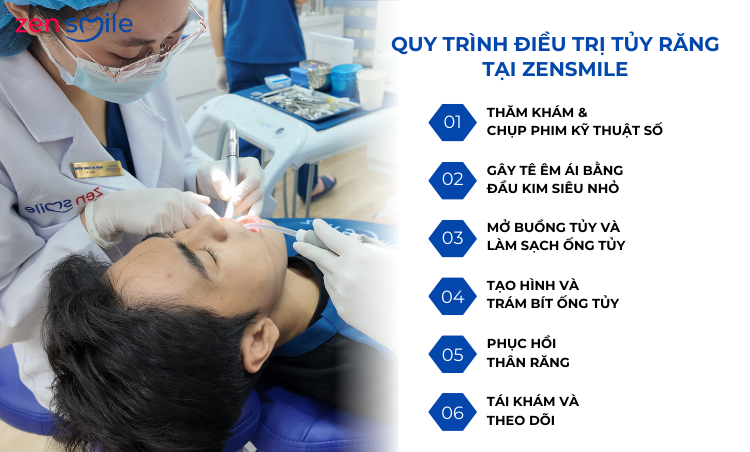

3. Quy trình điều trị tủy răng sữa tại Zensmile

Zensmile áp dụng quy trình điều trị tuỷ răng sữa theo hướng êm ái – tâm lý – an toàn cho trẻ:

👉 Bước 1: Thăm khám & chụp phim cần thiết

Bác sĩ đánh giá mức độ viêm tuỷ, tình trạng chân răng và mầm răng vĩnh viễn bên dưới.

👉 Bước 2: Gây tê nhẹ nhàng – tạo cảm giác an tâm

Sử dụng kỹ thuật gây tê phù hợp với trẻ, thao tác nhanh, hạn chế sợ hãi.

👉 Bước 3: Làm sạch tuỷ viêm

Loại bỏ phần tuỷ bị viêm hoặc hoại tử, làm sạch buồng tuỷ và ống tuỷ.

👉 Bước 4: Trám tuỷ bằng vật liệu chuyên dụng cho răng sữa

Vật liệu có khả năng tiêu sinh lý theo thời gian, không ảnh hưởng mầm răng vĩnh viễn.

👉 Bước 5: Phục hồi thân răng

Trám hoặc bọc mão răng sữa (nếu cần) để bảo vệ răng và đảm bảo chức năng ăn nhai.

👉 Bước 6: Hướng dẫn chăm sóc & theo dõi định kỳ

Cha mẹ được hướng dẫn vệ sinh, chế độ ăn và lịch tái khám phù hợp cho trẻ.

Quy trình điều trị tủy răng tại Zensmile